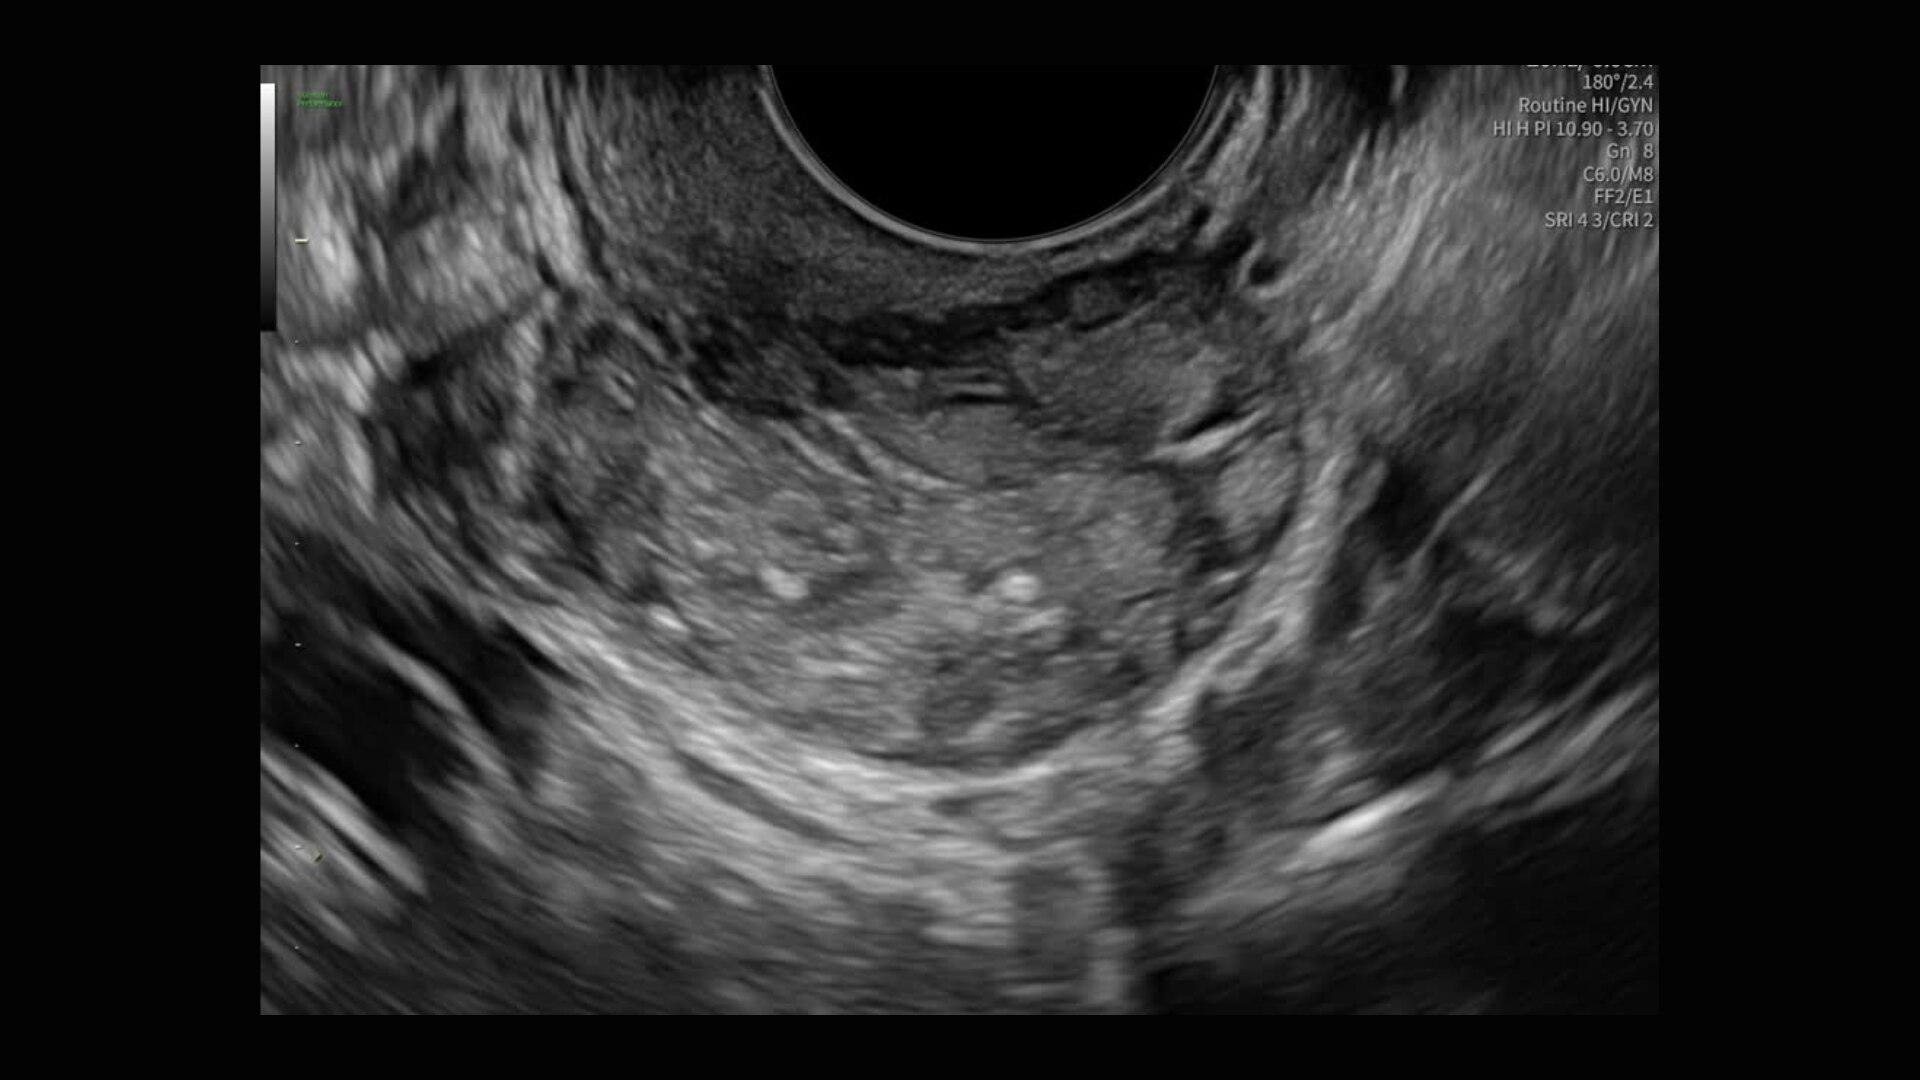

Image quality

Excellent images that are easy to acquire

Image quality is everything in ultrasound

The Voluson Performance 18 delivers high-resolution, detailed imaging with one-touch optimization for effortless scanning—helping you deliver quick, confident answers across a wide range of patient.